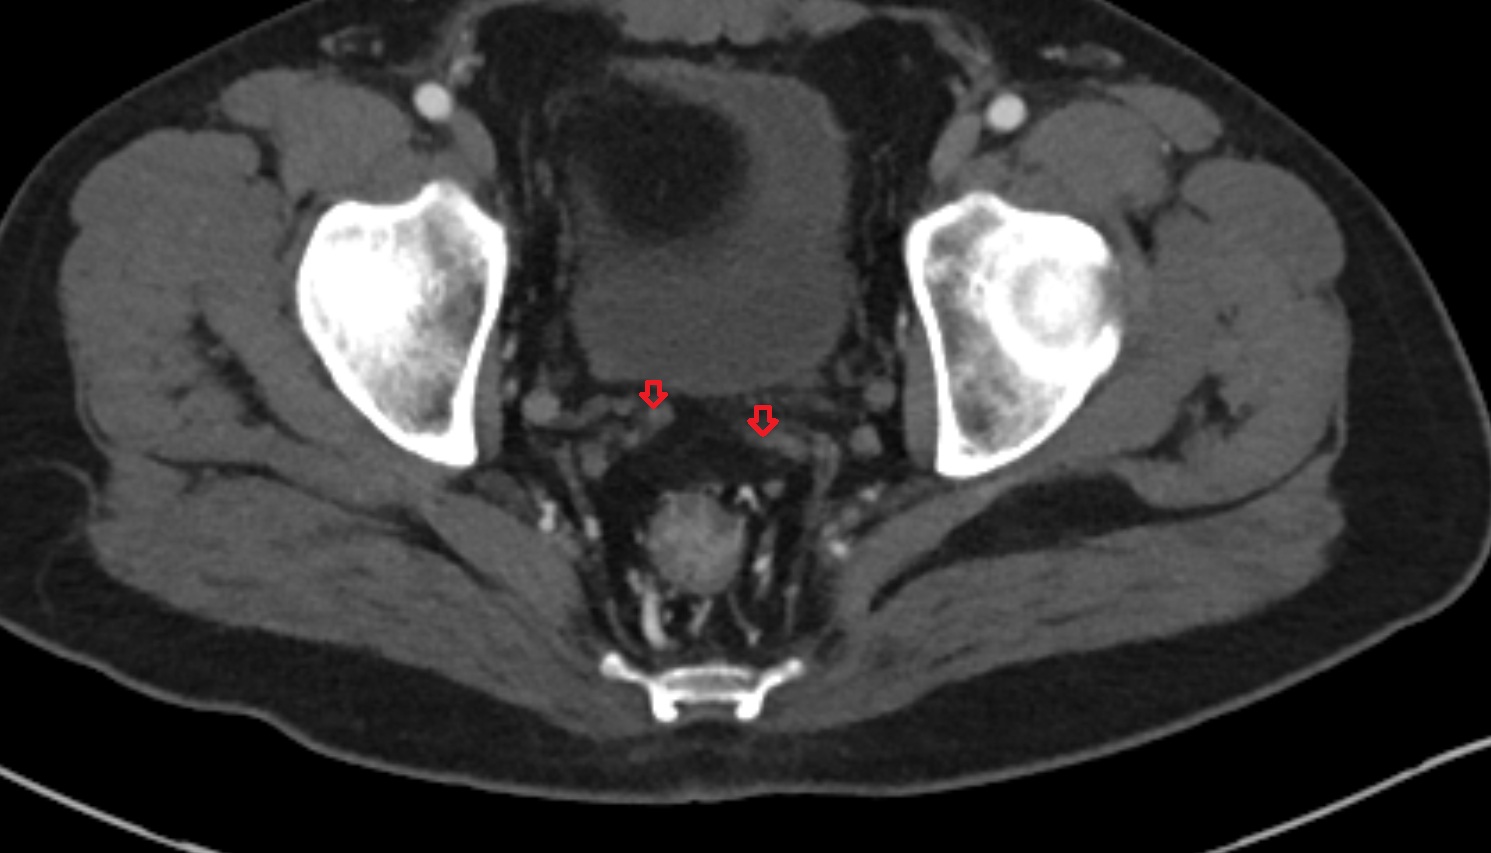

- Inguinal lymph nodes

- Intermediate lacunar external iliac lymph nodes

- External iliac lymph nodes

- Obturator lymph nodes